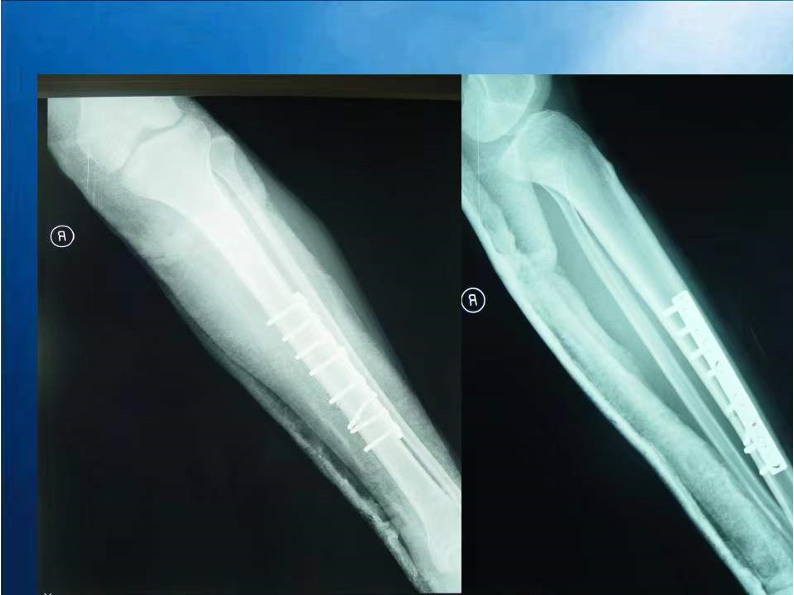

胫腓骨骨折